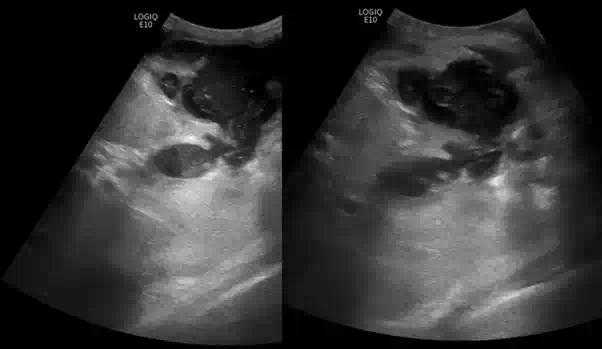

Längsschnitt über der Gallenblase

Lageverschieblichkeit zweier Gallenblasenkonkremente mit akuter Cholezystitis

Im Längsschnitt über die Gallenblase erkennt man auf dem linken Bild neben einer verdickten Gallenblasenwand zwei Konkremente, die sich am Ausgang der Gallenblase, dem sogenannten Infundibulum (lat. Trichter), befinden. Lässt man den Patienten aufstehen, wie rechts im Bild dargestellt, fällt eines der Konkremente der Schwerkraft folgend in den Fundus der Gallenblase, während das zweite weiterhin im Infundibulum eingeklemmt bleibt.

Da die Gallenblase auch ohne Zufluss aus der Leber ständig Sekrete in ihr Lumen absondert, steigt bei einem blockierten Ausgang der intraluminale Druck kontinuierlich an. Steigt der Druck in der Gallenblasenwand, kollabieren zunächst die venösen Gefäße. Bei weiterhin bestehendem arteriellem Zustrom fällt dadurch der venöse Abfluss aus, was zu einer zunehmenden Kongestion und weiteren Wandschwellung führt.

Mit fortschreitender Druckerhöhung wird schließlich auch der arterielle Perfusionsdruck erreicht, wodurch auch die Arterien komprimiert werden. Ab diesem kritischen Punkt ist die Gallenblase vollständig von der Blutversorgung abgeschnitten und es entwickelt sich eine ischämische Nekrose der Gallenblasenwand. Unbehandelt kann dies zu Perforation, Peritonitis und septischen Komplikationen führen, weshalb die frühzeitige sonographische Diagnose und rechtzeitige Intervention von entscheidender Bedeutung sind. Die dargestellte fehlende Lageänderung eines der Konkremente bei Positionswechsel ist  daher ein wichtiges diagnostisches Zeichen zum Beweis einer Obstruktion des Infundibulums